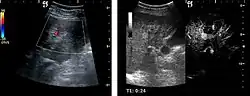

HCC appearance on 2D ultrasound is that of a solid tumor, with imprecise delineation, with heterogeneous structure, uni- or multilocular (encephaloid form). An "infiltrative" type is also described which is difficult to discriminate from liver nodular reconstruction in cirrhosis. Typically HCC invades liver vessels, primarily the portal veins but also the hepatic veins . Doppler examination detects a high speed arterial flow and low impedance index (correlated with described changes in tumor angiogenesis). The spatial distribution of the vessels is irregular, disordered. CEUS examination shows hyperenhancement of the lesion during the arterial phase. During the portal venous phase there is a specific "wash out" of ultrasound contrast agent (UCA) and the tumor appears hypoechoic during the late phase. Poorly differentiated tumors may have a stronger wash out leading to an isoechoic appearance to the liver parenchyma during portal venous phase. This appearance was found in approx. 30% of cases. The described changes have diagnostic value in liver nodules larger than 2 cm.

Ultrasound is useful in HCC detection, stadialization and assessing therapeutic efficacy. In terms of staging related to therapy effectiveness, the Barcelona classification is used which identifies five HCC stages. Curative therapy is indicated in early stages, which include very early stage (single nodule <2 cm), curable by surgical resection (survival 50-70% five years after surgical resection) and early stage (single nodule of 2–5 cm, or up to 3 nodules <3 cm) which can be treated by radiofrequency ablation (RFA) and liver transplantation. Intermediate stage (polinodular, without portal invasion) and advanced stage (N1, M1, with portal invasion) undergo palliative therapies (TACE and sorafenib systemic therapy) and in the end stage only symptomatic therapy applies.